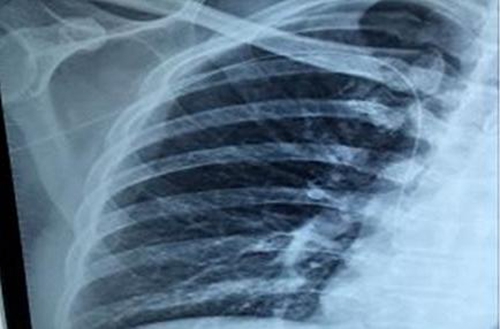

院综合科成功开展成人PICC置管术

日前,我院综合科护理团队成功开展首例成人B超引导下塞丁格技术PICC置管术,目前患者情况良好,这是我院继新生儿PICC技术后的又一次突破,标志着我院PICC护理技术水平又上了一个新台阶。

PICC是一种经外周静脉插入并开口于上腔静脉的导管,目前已成为发达国家和地区继中心静脉导管之后的又一种极其重要的输液途径和方式。我院成人PICC技术在临床特别是在肿瘤化疗患者中的应用,可减轻肿瘤患者长期化疗反复外周静脉穿刺的痛苦,解决此类患者去外地就医置管、维护的难题,同时也方便了外地带管患者到我院做正确维护,受到医患的一致好评。